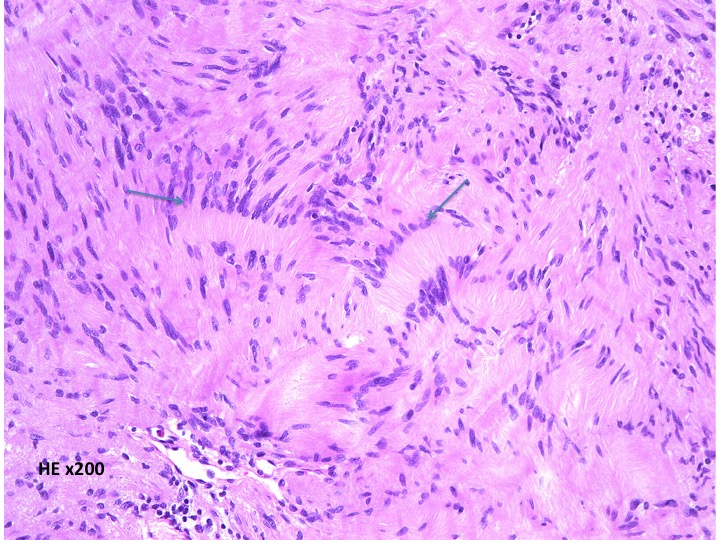

細胞核の柵状配列 (矢印 nuclear palisading). HE x200

細胞核が円状に並んだ形態で、いわゆるVerocay bodyと呼ばれる所見(矢印)。 HE x200.

隣り合う細胞核の柵状配列 nuclear palisade arrangement (palisading) は,髄膜腫との鑑別での大切な所見です。